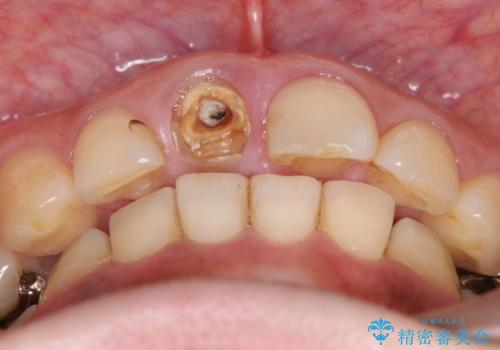

折れてしまった前歯 オールセラミックによる審美改善

- 「野菜をかじった際に前歯がぐらつき、その場で取れてしまった。前歯を入れたい。」と希望され来院されました。

残っている歯質(歯の量)は非常に少ないものの、歯を抜かずに残したい希望が強く、また破折リスクが高いことも

ご理解いただいた上で歯を残しセラミック治療を計画します。

破折リスクを少なくするため前歯でかじったり硬いものを噛み切る等の行為は避けた方が良いとお伝えし、現状5年問題なく経過しています。